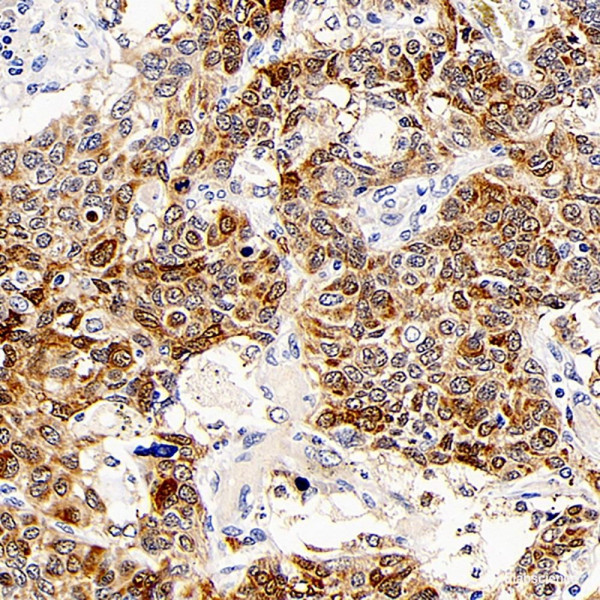

Product information "Anti-CD107b"

Lysosomal-associated membrane protein 2 (LAMP2,synonyms: LAMPB,CD107b) is a member of a family of membrane glycoproteins. This glycoprotein provides selectins with carbohydrate ligands. LAMP2 may plays a role in tumor cell metastasis. It may also functions in the protection,maintenance,and adhesion of the lysosome. Prior to posttranslational modification,LAMP2 is a ~45 kDa polypeptide. Mature,functional LAMP2 is extensively glycosylated with a variety of different N linked and O linked oligosaccharides. Protein function: Plays an important role in chaperone-mediated autophagy, a process that mediates lysosomal degradation of proteins in response to various stresses and as part of the normal turnover of proteins with a long biological half-live (PubMed:8662539, PubMed:11082038, PubMed:18644871, PubMed:24880125, PubMed:27628032). Functions by binding target proteins, such as GAPDH and MLLT11, and targeting them for lysosomal degradation (PubMed:8662539, PubMed:11082038, PubMed:18644871, PubMed:24880125). Plays a role in lysosomal protein degradation in response to starvation. Required for the fusion of autophagosomes with lysosomes during autophagy (PubMed:27628032). Cells that lack LAMP2 express normal levels of VAMP8, but fail to accumulate STX17 on autophagosomes, which is the most likely explanation for the lack of fusion between autophagosomes and lysosomes (PubMed:27628032). Required for normal degradation of the contents of autophagosomes (PubMed:27628032). Required for efficient MHCII-mediated presentation of exogenous antigens via its function in lysosomal protein degradation, antigenic peptides generated by proteases in the endosomal/lysosomal compartment are captured by nascent MHCII subunits (PubMed:20518820). Is not required for efficient MHCII-mediated presentation of endogenous antigens (PubMed:20518820). [The UniProt Consortium]

| Application: | IHC |